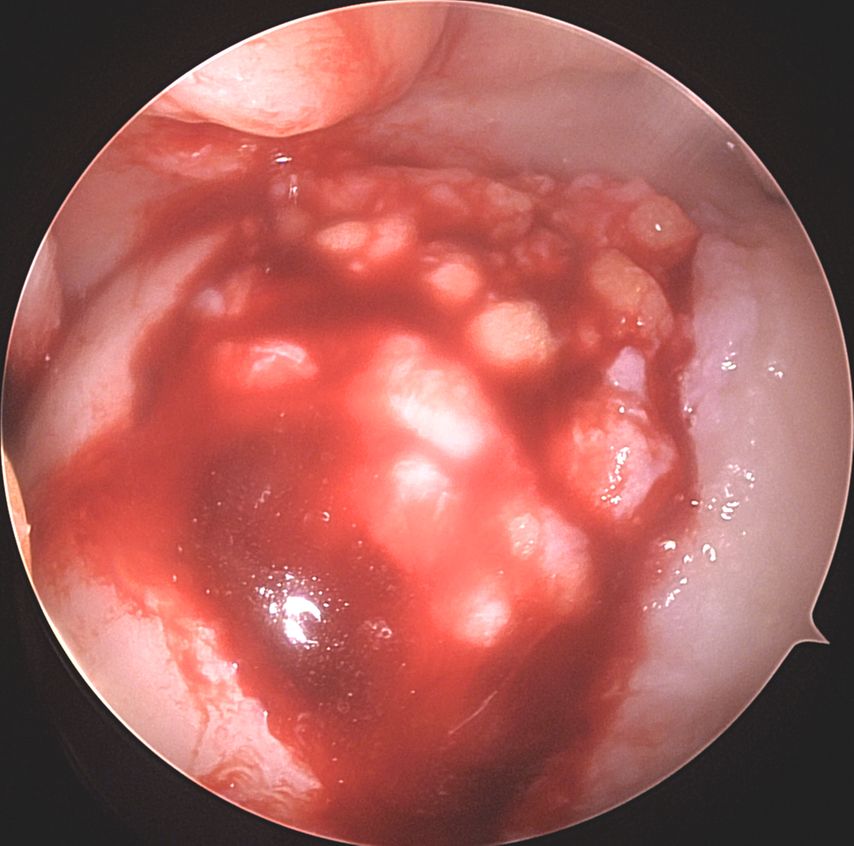

Abb. 1a und b: MRI-Bildgebung präoperativ bei grossem, vollflächigem Knorpelschaden an der medialen Femurkondyle einer jungen Patientin

Abb. 1c: Intraoperatives arthroskopisches Bild des Knorpeldefektes nach Debridement an der medialen Femurkondyle Knie links, Defekt 2 x 3cm = 6cm2